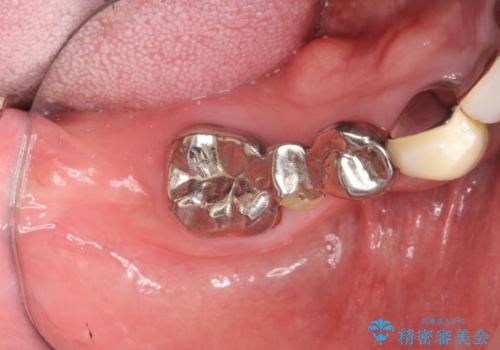

- 「歯がぐらぐらして噛めない、歯を抜いて欲しい、またしっかりと噛めるようになりたい。」、と歯周病治療を希望され来院されました。

歯の根本まで骨吸収が進み、ぐらぐらになってしまった歯を抜去し骨の造成を行ったのちインプラント治療を計画します。

重度に吸収してしまった歯槽骨をしっかりと造成を行ったのちにインプラント治療を行ったので、安定した歯周環境にすることができました。